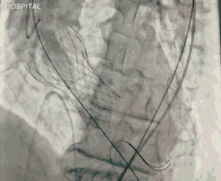

今天直播的这位患者是85岁的老年男性,10年前因主动脉瓣重度狭窄植入CoreValve 26mm瓣膜,是我国第一例TAVR患者,术后恢复情况良好。

6个月之前,患者出现反复胸闷气急,心超提示人工生物主动脉瓣置换术后,中重度主动脉瓣口反流,轻度瓣周漏。这例患者目前已85岁,同时合并持续性房颤、高血压、心功能不全Ⅲ级,STS评分7.56%,外科手术风险高危。

葛均波院士、周达新教授结构团队对这位生物瓣衰败的老年男性患者行瓣中瓣植入术,术中选择了23mm VenusA-Valve(杭州启明),植入过程顺利,术后冠脉无堵塞,未出现瓣周漏,术后跨瓣压差接近于0,赢得了参会专家的激烈掌声。

图3 TAVR瓣膜释放前造影

图4 TAVR球囊前扩张

图5 TAVR瓣膜释放后